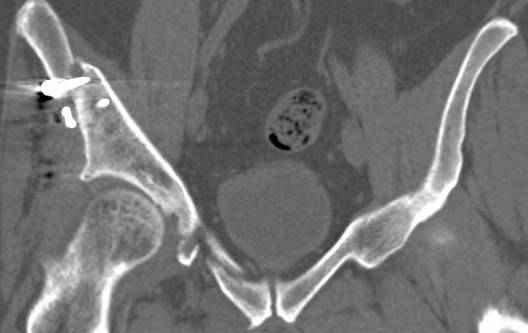

Интересно было бы посмотреть рентгенограммы до операции. У меня впечатление, что я не все вижу, что тут есть... Уважаемые Господа "тазисты" и "тазологи", к какому типу переломов вертлужной впадины по Летурнелю вы бы отнесли это случай?

Из переломов проходящих через крыло и/или заднюю стенку ни простой перелом "передней колонны" (явно имеется пером задней стенки, и не видно перелома седалищной или лонной), ни простой "поперечный", ни ассоциированный "Т-образный" (т.к есть перелом крыла и не видно перелома седалишной), ни ассоциированный "задняя колонна+задняя стенка", на ассоциированный "поперечный+задняя стенка", ни ассоциированный "передняя колонна+задняя гемисфера" (не видно перелома седалищной), ни ассоциированный "обе колонны" (не видно перелома лонной седалищной) не подходят под эту классификацию....

к таковым себя не причисляю, но...обычное дело для нашей страны - выкладывать 3D и не показывать стандартные проекции Judet. Дигност представляет те ракурсы, которые по-его мнению наиболее информативны, более того комп сам достраивает какие-то мелкие повреждения по 3D по своему усмотрению. По данной реконструкции можно предполагать высокий двухколонный перелом с оскольчатыми передней и задней колоннами, оскольчатую высокую переднюю колонну с задним полупоперечником или одно из перечисленных с вовлечение КПС. У меня впечатление за второй вариант, но нужно обследовать нормально - проекции, сканы.

высылаю дополнительно сканы.

итак, второй вариант: высокий двухколонный с вовлечением КПС... Ни одно из основных повреждений не репонировано, кроме задней стенки. Скорее всего попытка реконструкции вертлуги сейчас будет очень травматичной и не очень эфективной, т.е. вероятный риск более значим, чем ожидаемая польза... Лучше подождать, и потом сразу эндопротез

подождать сколько, чего? такая дыра в задней колонне не закроется никогда.

потом эндопротез какой? в такой ситуации приходит на ум Burch-Schneider cage, в 35 лет, дальше что делать?